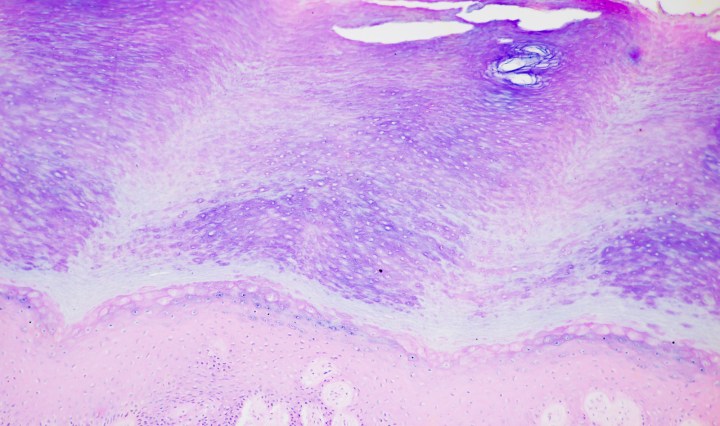

Stratified Squamous epithelium, Keratinized

August 14, 2016September 3, 2016 Kit Ng

Stratified epithelium is classified by the cell type on the uppermost layer.  Notice that is true for the pictures shown below.  They are typically found in locations where constant abrasion is likely, such as skin.  The epithelium at these locations … Continue reading Stratified Squamous epithelium, Keratinized

Stratified Squamous Epithelium, non-Keratinized

August 12, 2016August 14, 2016 Kit Ng

Stratified epithelium is classified by the cell type on the uppermost layer.  Notice that is true for the pictures shown below.  They are typically found in locations where constant abrasion is likely, such as mouth, esophagus and vagina.  The epithelium … Continue reading Stratified Squamous Epithelium, non-Keratinized